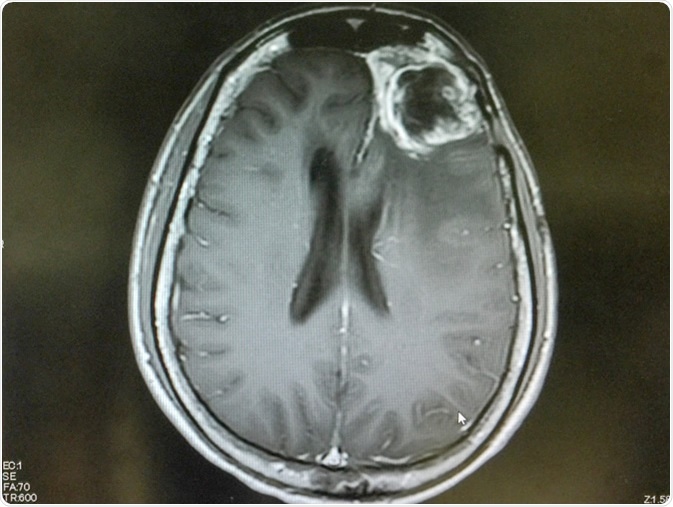

MRI brain show left frontal gliblastoma. Image Credit: O_Akira / Shutterstock